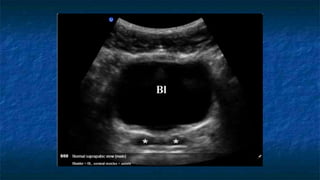

3)FAST: Pelvis exam

 Pelvis: Longitudinally and Transvers Axis.

 Probe placed

 Transeversally then Longitudinally

 Midline 2 cm superior to the symphysis pubis

 “aimed” caudally into the pelvis (prostate )

 Probe facing

 Toward patient’s head and right side.

 Best with some urine in bladder(acoustic window)

 Evaluating

 Bladder ,Uterus in female ,and Prostate in

male

 The potential spaces are Pouch of

Douglas (Cul de sac ) in female and

retrovesicle space in male

FAST: Pelvis exam

 Pelvis: Transverse Axis

 Normal Anatomy

 Evaluating Bladder

 Well cirucumscribed

 Contains fluid that

appears anechoic

Transverse